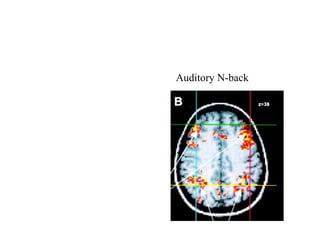

• DLPFC and working memory ( Nystrom et

al ‘00))

Auditory N-back

• DLPFC andworking memory ( Nystrom et al ‘00))